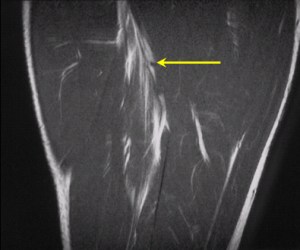

Injury example: a strain to the long head of biceps femoris (hamstrings)